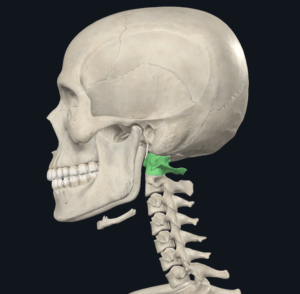

頭蓋骨を支える第一頸椎であるAtlas(C1)と第二頸椎であるAxis(C2)から構成される上部頸椎のミスアライメントは、めまい、ブレインフォグ、離人症、認知機能および見当識障害(認知症症状)、メニエール病、良性発作性頭位めまい症、迷走神経性失神、自律神経機能障害、頭の中の圧迫感、頭がいっぱいになる頭痛、前頭部が重くなる頭痛、頭がぼんやりする状態、頭の中がもやもやして集中できない状態、後頸部と肩の痛みなど、様々な疾患において隠れた原因となっている場合が多くあります。